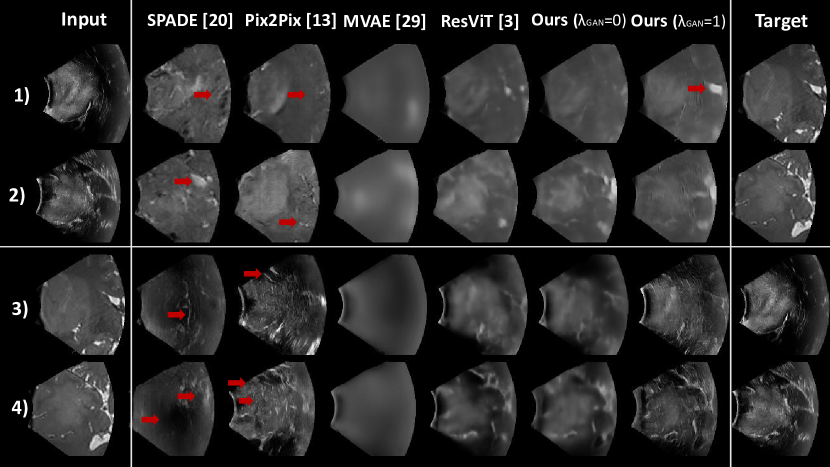

Refer to caption

Figure 2: Examples of image synthesis (rows 1 and 2: iUST2iUST2\text{iUS}\rightarrow\text{T}\textsubscript{2}; rows 3 and 4: T2iUST2iUS\text{T}\textsubscript{2}\rightarrow\text{iUS}) using SPADE [22], Pix2Pix [14], MVAE [31], ResViT [4] and MHVAE (ours) without and with GAN loss. As highlighted by the arrows, our approach better preserves anatomy compared to GAN-based approach and produces more realistic approach than the transformer-based approach (ResViT).

To quantify the importance of each component of our approach, we conducted an ablation study. First, our model (MHVAE) was compared with MVAE, the non-hierarchical multi-modal VAE described in [31]. It can be observed in Table 1 that MHVAE (ours) significantly outperformed MVAE. This highlights the benefits of introducing a hierarchy in the latent representation. As shown in Fig.2, MVAE generated blurry images, while our approach produced sharp and detailed synthetic images. Second, the impact of the GAN loss was evaluated by comparing our model with (λGAN=0subscript𝜆GAN0\lambda_{\text{GAN}}=0) and without (λGAN=1subscript𝜆GAN1\lambda_{\text{GAN}}=1) the adversarial loss. Both models performed similarly in terms of evaluation metrics. However, as highlighted in Fig. 2, adding the GAN loss led to more realistic textures with characteristic iUS speckles on synthetic iUS. Finally, the image similarity between the target and reconstructed images (i.e., target image used as input) was excellent, as highlighted in Table 1. This shows that the learned latent representations preserved the content information from input modalities.

4.0.5 State-of-the-art comparison.

To evaluate the performance of our model (MHVAE) against existing image synthesis frameworks, we compared it to two state-of-the-art GAN-based conditional image synthesis methods: Pix2Pix [14] and SPADE [22]. These models have especially been used as synthesis backbones in previous MR/iUS synthesis studies [6, 15]. Results in Table 1 show that our approach statistically outperformed these GAN methods with and without adversarial learning. As shown in Fig. 2, these conditional GANs produced realistic images but did not preserve the brain anatomy. Given that these models are not unified, Pix2Pix and SPADE must be trained for each synthesis direction (T2iUST2iUS\text{T}\textsubscript{2}\rightarrow\text{iUS} and iUST2iUST2\text{iUS}\rightarrow\text{T}\textsubscript{2}). In contrast, MHVAE is a unified approach where one model is trained for both synthesis directions, improving inference practicality without a drop in performance. Finally, we compared our approach with ResViT [4], a transformer-based method that is the current state-of-the-art for unified multi-modal medical image synthesis. Our approach outperformed or reached similar performance depending on the metric. In particular, as shown in Fig. 2 and in Table. 1 for the perceptual LPIPS metric, our GAN model synthesizes images that are visually more similar to the target images. Finally, our approach demonstrates significantly lighter computational demands when compared to the current SOTA unified image synthesis framework (ResViT), both in terms of time complexity (8G MACs vs. 487G MACs) and model size (10M vs. 293M parameters). Compared to MVAEs, our hierarchical multi-modal approach only incurs a marginal increase in time complexity (19%percent1919\%) and model size (4%percent44\%). Overall, this set of experiments demonstrates that variational auto-encoders with hierarchical latent representations, which offer a principled formulation for fusing multi-modal images in a shared latent representation, are effective for image synthesis.